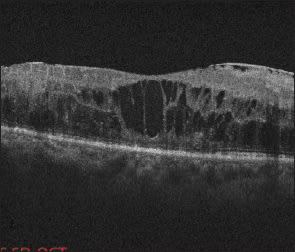

1. Wet AMD: OCT vs. FA with SLO

Most Optimal Technique

Advantages: Allows for quantification of retinal thickness; easy and quick; non-invasive.

Limitations: Need SD-OCT to see small (<10 µm) lesions.

Alternative Technique

Advantages: Follow leakage; classify NV membranes as classic or occult.

Limitations: Longer test; invasive; requires more patient cooperation; may not see anti-VEGF response as clearly.